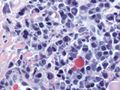

| Micrograph of a plasmacytoma. H&E stain | |

Bone marrow aspirate showing the histologic correlate of multiple myeloma under the microscope. H&E stain.